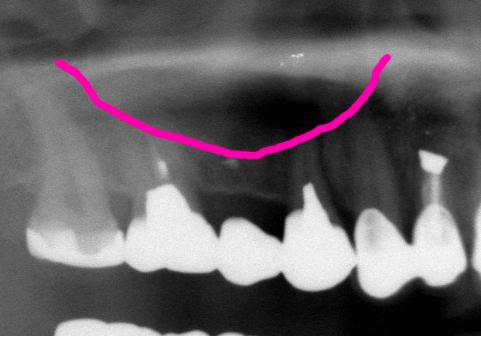

術前術前骨の高さが不足している場合、通常のインプラントでは処置が不可能なものが多い。特殊なショートインプラントを用いて可能になる例。 術前 術前CT像術前CT像術前CT像、下歯槽神経が下あごの中央部を走行しているため利用できる骨の高さが少ない。 埋入予定計画埋入予定計画埋入予定計画 術後レントゲン術後レントゲン、ひだりは少し神経をおそれすぎてやや埋入深度が不足、しかしこれでもしっかりと骨と固着した。